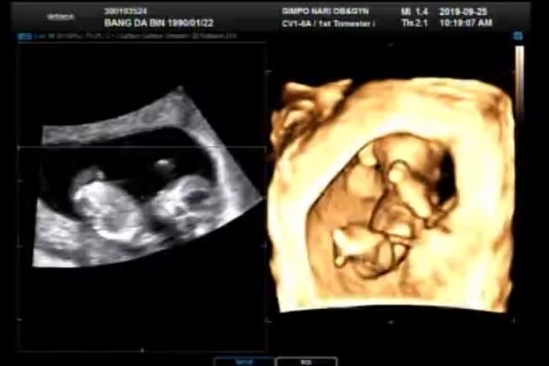

[임신 9주~12주] 임신 중 추석, 신랑 생일 & 1차 기형아 검사

이 맘 때쯤엔 입덧이 오락가락 했던 것 같아요~ 끝나 갈 것 같기도 하다가 여전한 울렁거림,,, 저녁 땐 어...